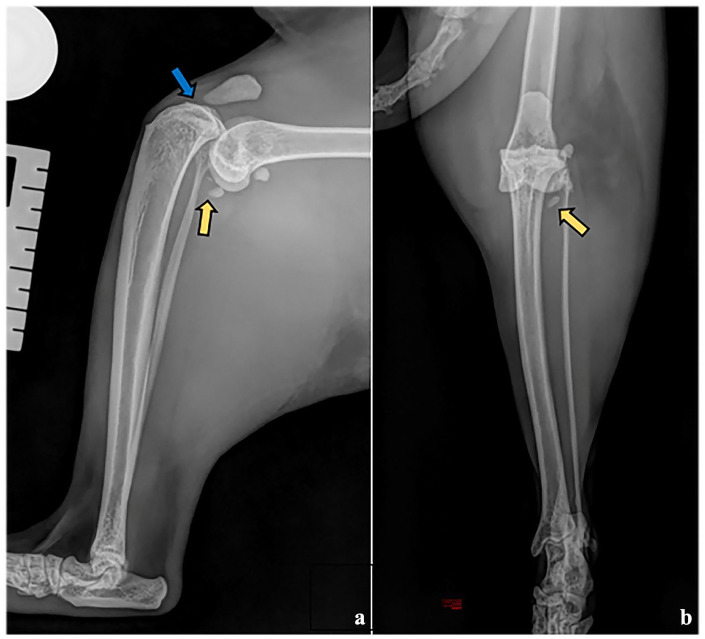

病例摘要:一只 11 岁的雌性阉割短毛猫因外伤性右跗关节松弛而转诊接受手术治疗。在全身麻醉的情况下,对患病跗关节进行了骨科检查,发现关节积液、颅尾和旋转不稳定。X光检查发现胫骨相对于股骨的头颅移位和髌下垫征。术中观察到两条十字韧带完全断裂,内侧和外侧半月板的中端和尾端明显断裂。两条副韧带看起来完好无损。切除了受伤的十字韧带残余部分,并进行了内侧和外侧尾骨半月板切除术。胫骨平台平整截骨术(TPLO)解决了胫骨头尾不稳的问题。术中对跗关节的评估显示,胫骨头侧平移、内旋和外旋以及尾侧牵引试验阳性的不稳定性持续存在。为解决持续存在的胫骨颅内翻和内旋问题,采用了外侧增强缝合术。为了成功中和因尾交叉韧带缺损而导致的颅内和外旋不稳定性,在三枚干扰螺钉的辅助下进行了内侧增强缝合。跗关节稳定得以实现。术后使用改良罗伯特-琼斯绷带包扎24小时。手术效果极佳,成功恢复了肢体功能:本病例报告首次记录了猫科动物外伤性跗关节松弛修复术,该手术结合了矫正性胫骨截骨术和关节外增高术。值得注意的是,该病例介绍了通过内侧和外侧增强缝合实施TPLO的新技术,以解决多向跗关节不稳定的问题。

Case summary: An 11-year-old female neutered domestic shorthair cat was referred for surgical management of a traumatic right stifle luxation. Orthopaedic examination of the affected stifle under general anaesthesia revealed joint effusion and craniocaudal and rotational instability. Cranial displacement of the tibia with respect to the femur and infrapatellar pad sign were identified on radiography. Intraoperatively, complete rupture of both cruciate ligaments and marked disruption of the mid and caudal poles of the medial and lateral menisci were observed. Both collateral ligaments appeared intact. The remnants of the injured cruciate ligaments were removed, and medial and lateral caudal hemimeniscectomies were performed. A tibial plateau levelling osteotomy (TPLO) was performed to address the craniocaudal stifle instability. Intraoperative assessment of the stifle revealed persistent instability with cranial tibial translation, internal and external rotation, and a positive caudal draw test. A lateral augmentation suture was employed to address the persistent cranial tibial translation and internal rotation. To successfully neutralise caudocranial and external rotational instability secondary to the caudal cruciate ligament deficiency, a medial augmentation suture was placed with the aid of three interference screws. Stifle stability was achieved. A modified Robert-Jones bandage was kept on for 24 h postoperatively. An excellent outcome was achieved, with successful limb function restoration.